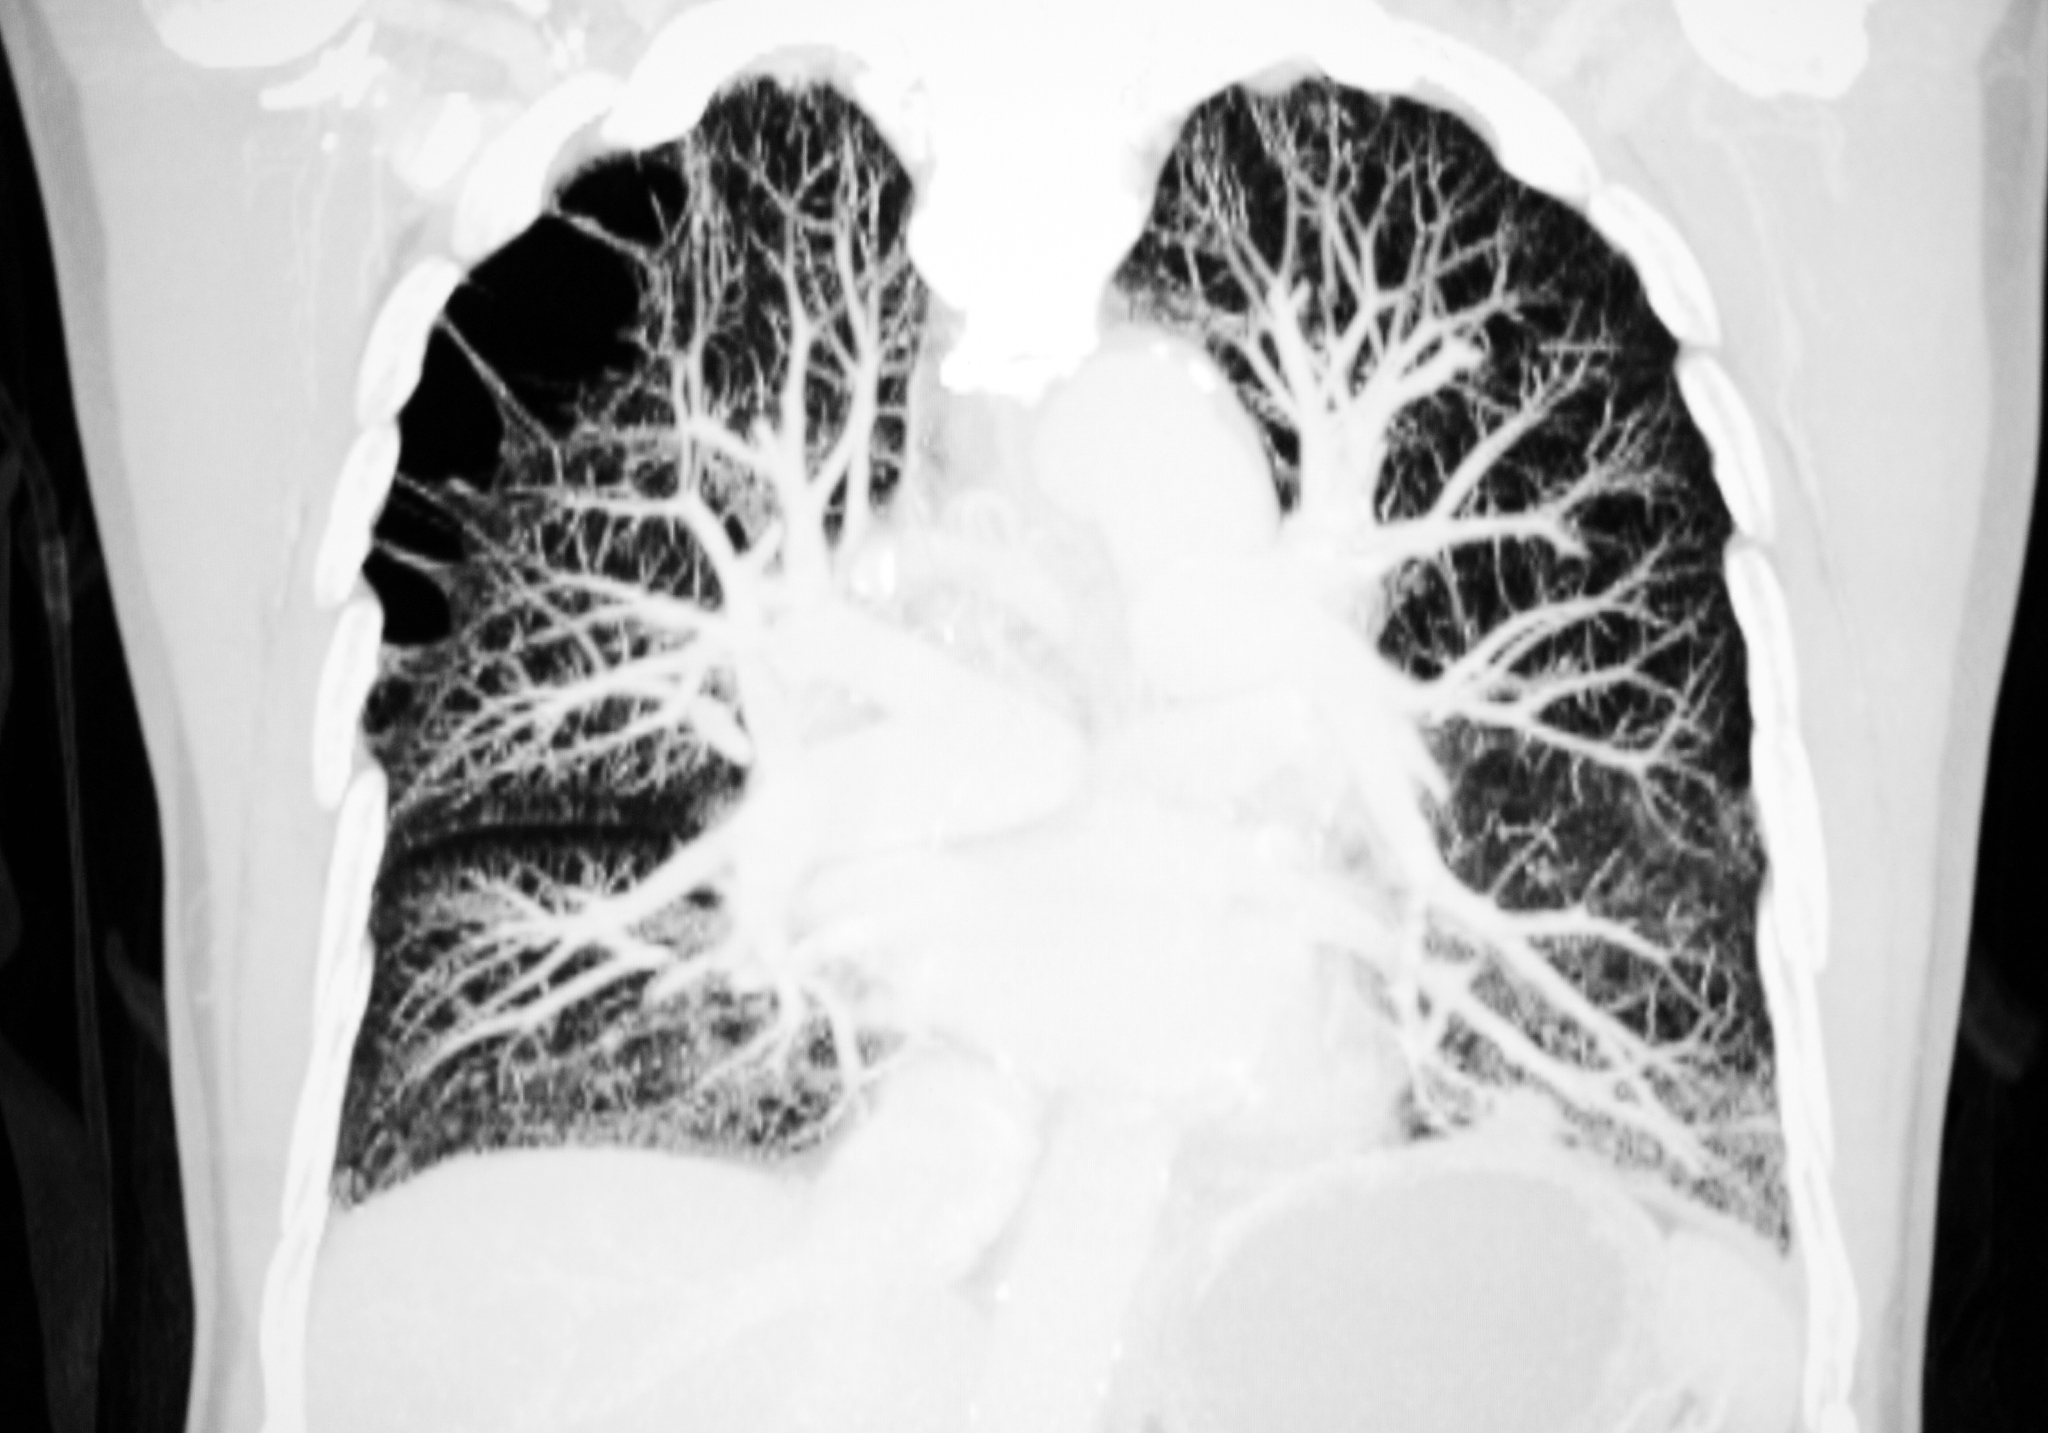

目前公开的肺部核磁共振图像数据集比较少,以下是一些常见的数据集:

需要注意的是,肺部核磁共振图像数据集相比于肺部CT图像数据集,数量较少且质量较低,因此在使用时需要注意数据的可靠性和准确性。

肺部核磁共振图像数据集 - 数量稀少,质量良莠不齐